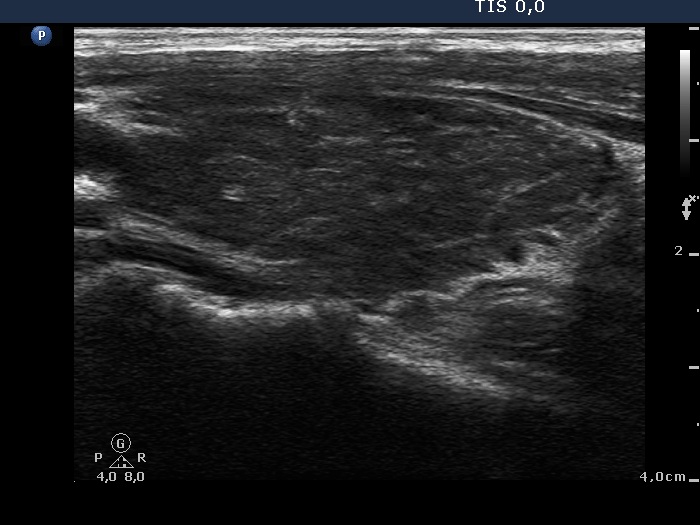

Graves' disease - Case 572 (ultrasonographic picture 5)

Left lobe, longitudinal scan.